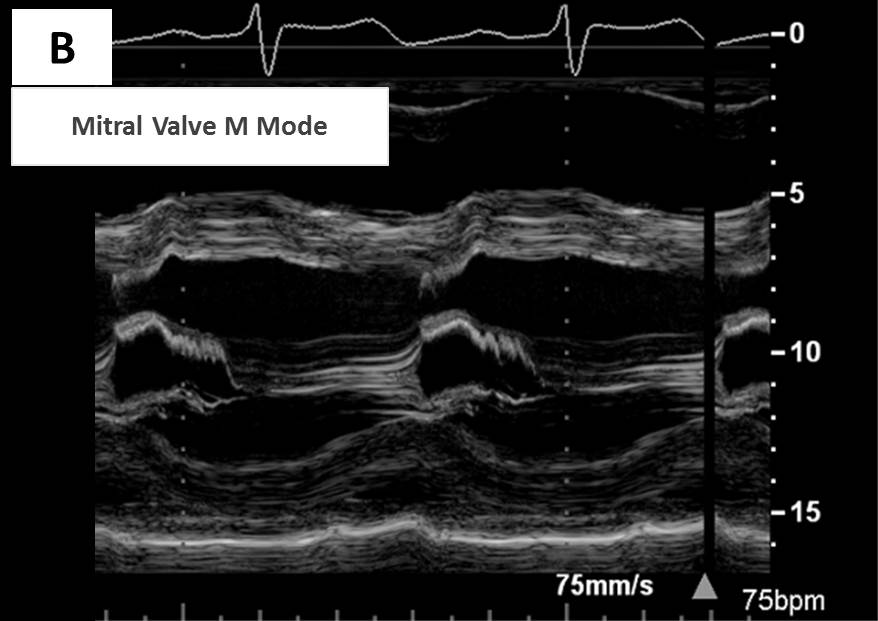

Explanation for Answer B

Due to a marked rise in LV diastolic pressure, the mitral valve closes prematurely, as shown in Figure 2 and lower panel of Figure 7. Note that in this patient, the mitral valve closes well before the QRS complex on the electrocardiogram. This is in contrast to the timing of mitral valve closure after the onset of the QRS in a healthy individual, as shown in the upper panel of Figure 7.

Figure 7